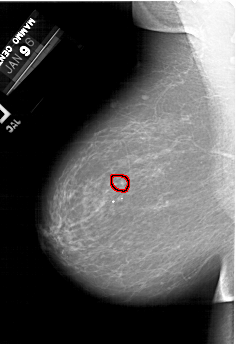

A_1492_1.LEFT_MLO

FILE: A_1492_1.LEFT_MLO.OVERLAY

TOTAL_ABNORMALITIES 1

ABNORMALITY 1

LESION_TYPE CALCIFICATION TYPE PUNCTATE DISTRIBUTION CLUSTERED

ASSESSMENT 4

SUBTLETY 3

PATHOLOGY BENIGN

TOTAL_OUTLINES 1

BOUNDARY